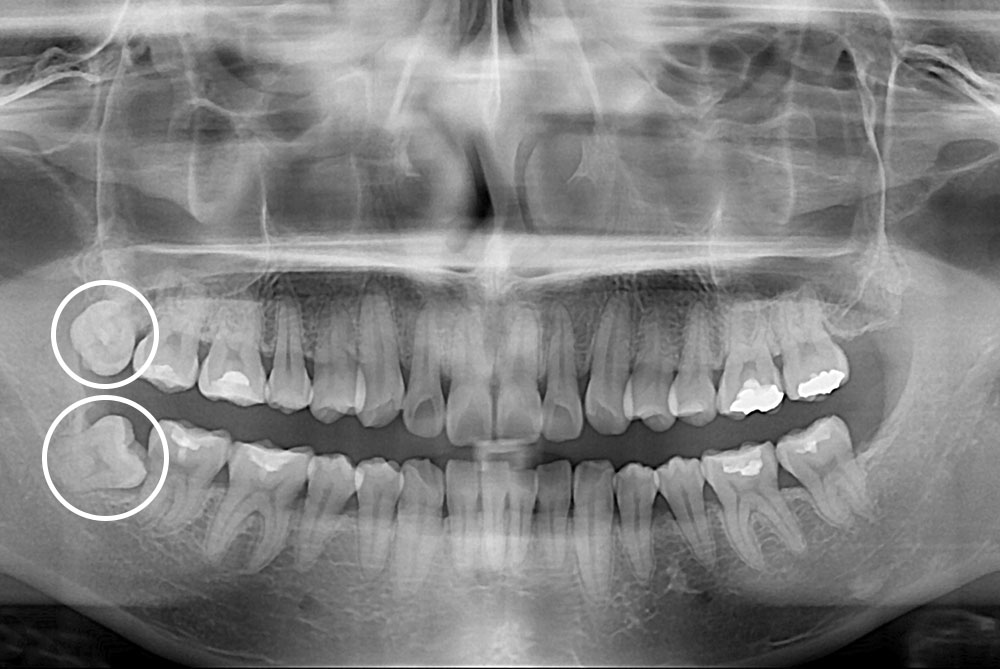

[사랑니] 매복 사랑니 발치

치료후 : 2019-02-22